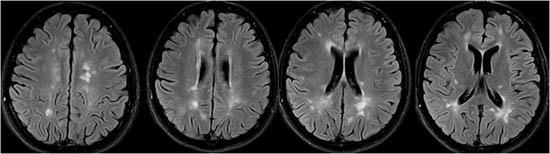

Ciertas enfermedades inflamatorias del sistema nervioso, como la esclerosis múltiple.

Resonancia Magnética cerebral. Lesiones típicas de esclerosis múltiple.